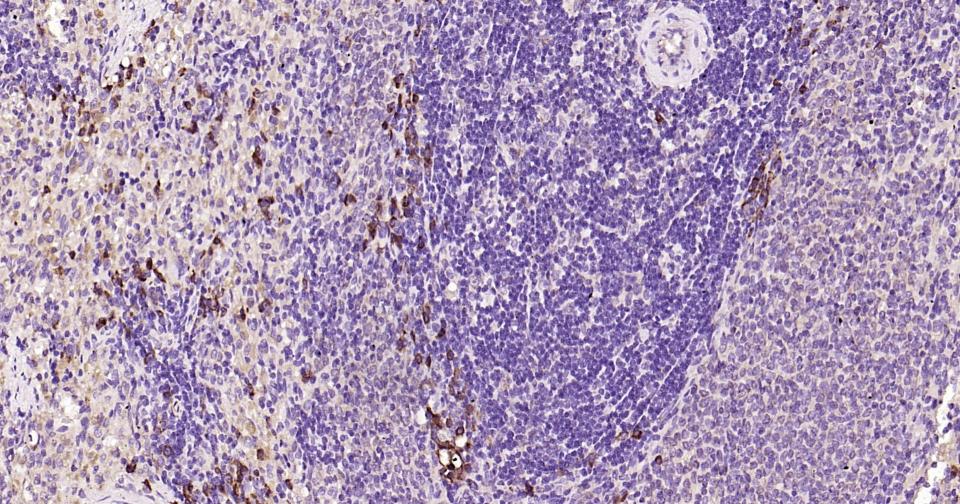

| 应用 | 已检合格种属 | 预测种属 | 推荐稀释比例 |

|---|---|---|---|

| IHC-P | Human, Mouse, Rat | 1:100-500 | |

| IHC-F | Human, Mouse, Rat | 1:100-500 | |

| IF | Human, Mouse, Rat | 1:100-500 |

交叉反应: Human, Mouse, Rat